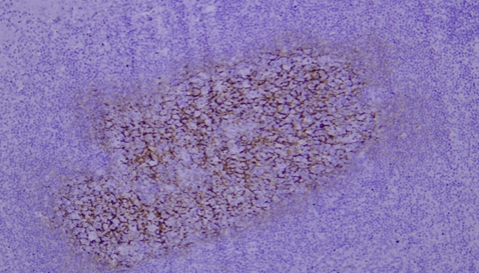

CD45 staining of paraffin-embedded human lymph node sections: Due to insufficient tissue fixation, lymphocytes at the edge of the lymph node show strong CD45 positivity, while those in the inner part of the tissue exhibit weak positivity, leading to uneven staining overall.